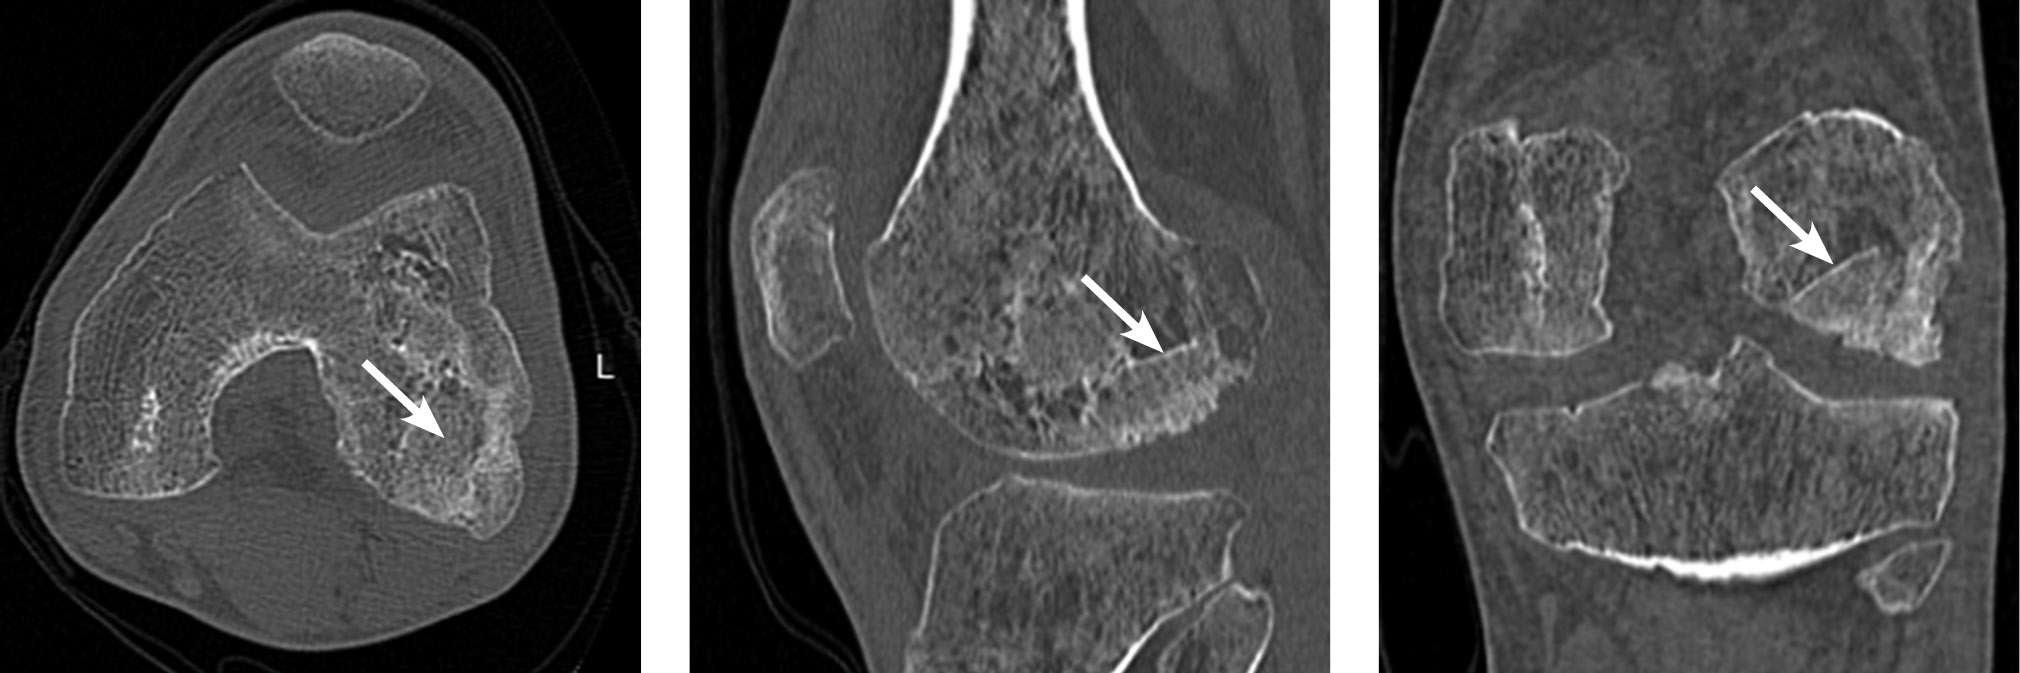

Radiographic evaluations—including X-ray, spiral computed tomography, and magnetic resonance imaging—identified an osteochondral defect in the central region of the medial femoral condyle, measuring 2.0 × 1.4 × 1.0 cm. The lesion was classified as a deep defect (ICRS grade IV). Postoperative changes were recorded, accompanied by synovitis of the right knee joint and early signs of secondary deforming osteoarthritis (stages I–II) (Fig. 1).

Fig. 1. Diagnostic imaging of patient B (age: 17 years at admission): a, X-ray of the right knee joint in anteroposterior and axial views; b, computed tomography scans exhibiting frontal, sagittal, and axial slices through the lesion; c, magnetic resonance imaging scans, frontal and sagittal views through the lesion. The area of destruction is indicated by an arrow.